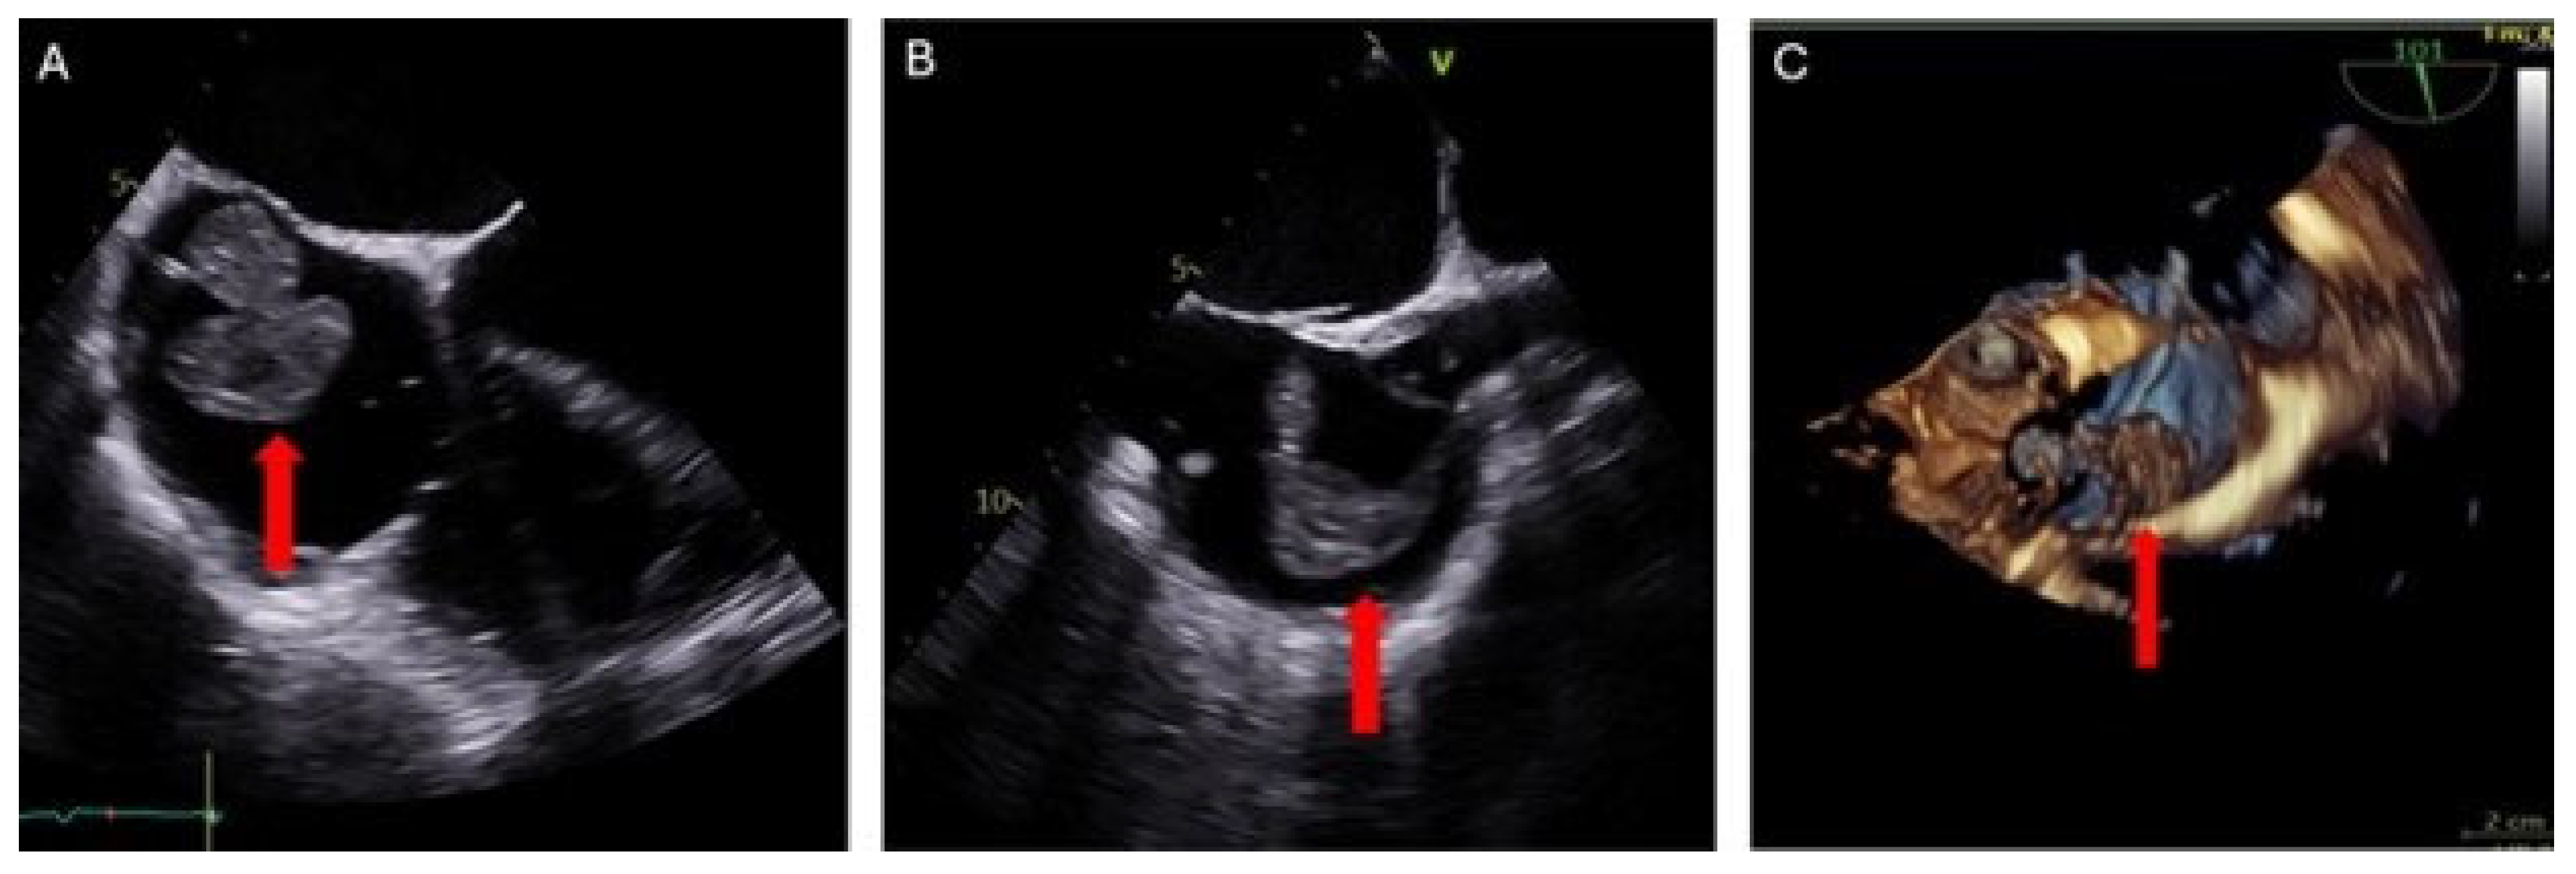

Evaluation was conducted using transesophageal echocardiography (TEE) preoperatively, intraoperatively, and postoperatively. Pre-procedure TEE revealed a large, multilobulated, and highly mobile right atrial mass attached by a thin stalk to the right atrial wall at the SVC-RA junction. The mass measured up to 37 × 31 mm (Figure 3). Moderate mitral valve regurgitation and mild-to-moderate tricuspid valve regurgitation were also noted. A patent foramen ovale (PFO) was not detected.

Figure 3. Transesophageal echocardiogram: (A) 2D 0° 4-chamber RV-focused view showing right atrial thrombus (red arrow). (B) 2D 101° bi-caval view confirming thrombus attachment at the SVC–RA junction (red arrow). (C) 3D image view illustrating the size and mobility of the right atrial thrombus (red arrow).